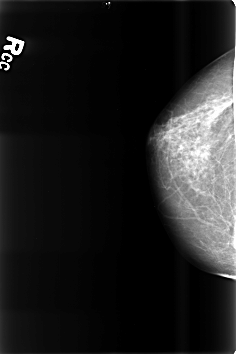

B_3471_1.RIGHT_MLO

RIGHT_CC LINES 4600 PIXELS_PER_LINE 3064 BITS_PER_PIXEL 12 RESOLUTION 50 NON_OVERLAY

RIGHT_MLO LINES 4576 PIXELS_PER_LINE 3064 BITS_PER_PIXEL 12 RESOLUTION 50 NON_OVERLAY